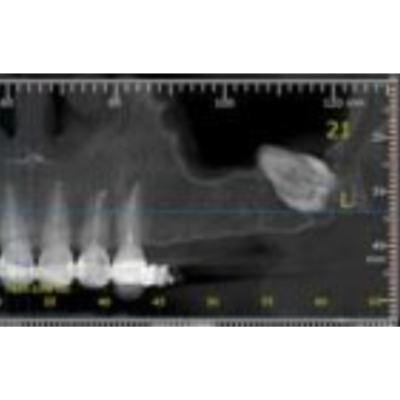

Hey, guys! Dragos from Romania here! I’ve made a bit of courage to start posting and asking about some of my cases (since i started doing them more frequently). Please don’t judge mistakes since I don’ t pretend to be a guru of surgery of some sort. Actually I still consider myself a begginer in that matter. Anyway, here’s a case I did this…

I have a follow up question: So she experienced her sinus symptoms 5 days after the procedure?